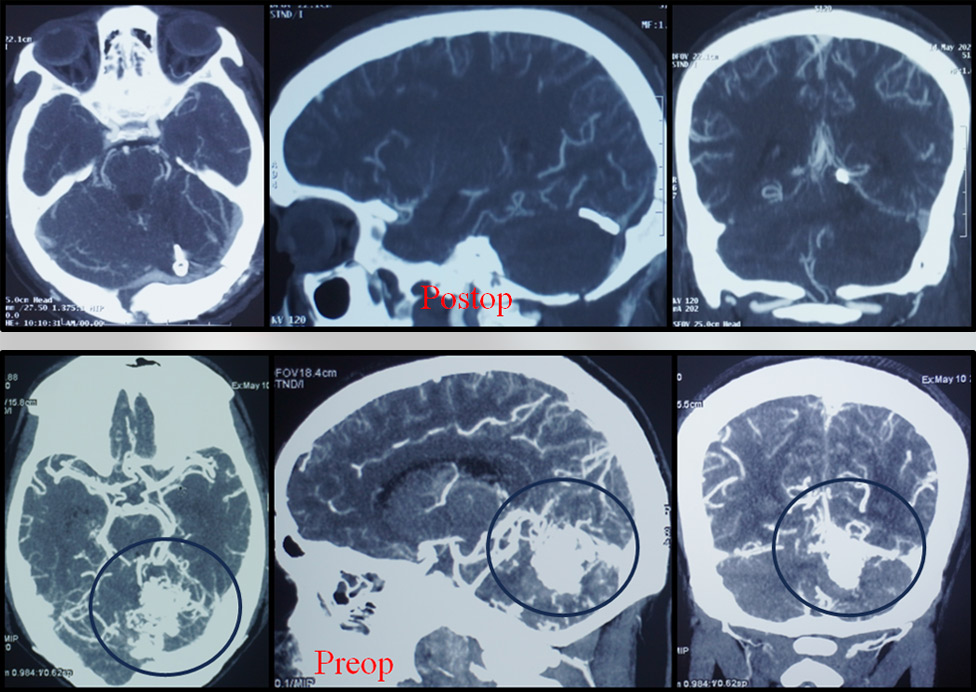

Moving ahead from facial preservation, hearing preservation in acoustic surgery always remains a challenge. With a good Cochlear nerve preservation rate and preserving useful hearing in almost one third cases, here I am presenting my latest case.

Though here, salvageable hearing was not present even in pre-op, but post-op Audiogram is showing absolutely untouched Cochlear nerve.